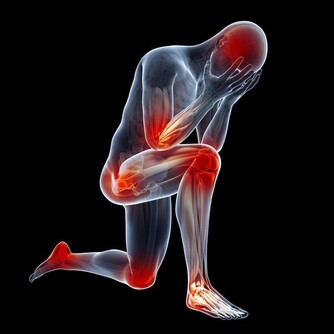

上海中醫藥大學附屬龍華醫院 脾胃病科副主任醫師柳濤稱,有一些患者,片面追求轉氨酶正常,服用一些降酶藥物,而忽視生活方式的改變。飲食控制和適量運動是預防和治療非酒精性脂肪肝的基石,除了按照醫囑治療外,根本上是要靠自己「管住嘴,邁開腿」。治療或預防脂肪肝需要合理飲食,控制食物攝入總量,少吃高脂肪、高熱量食物,加強有氧運動,持之以恆,循行漸進。